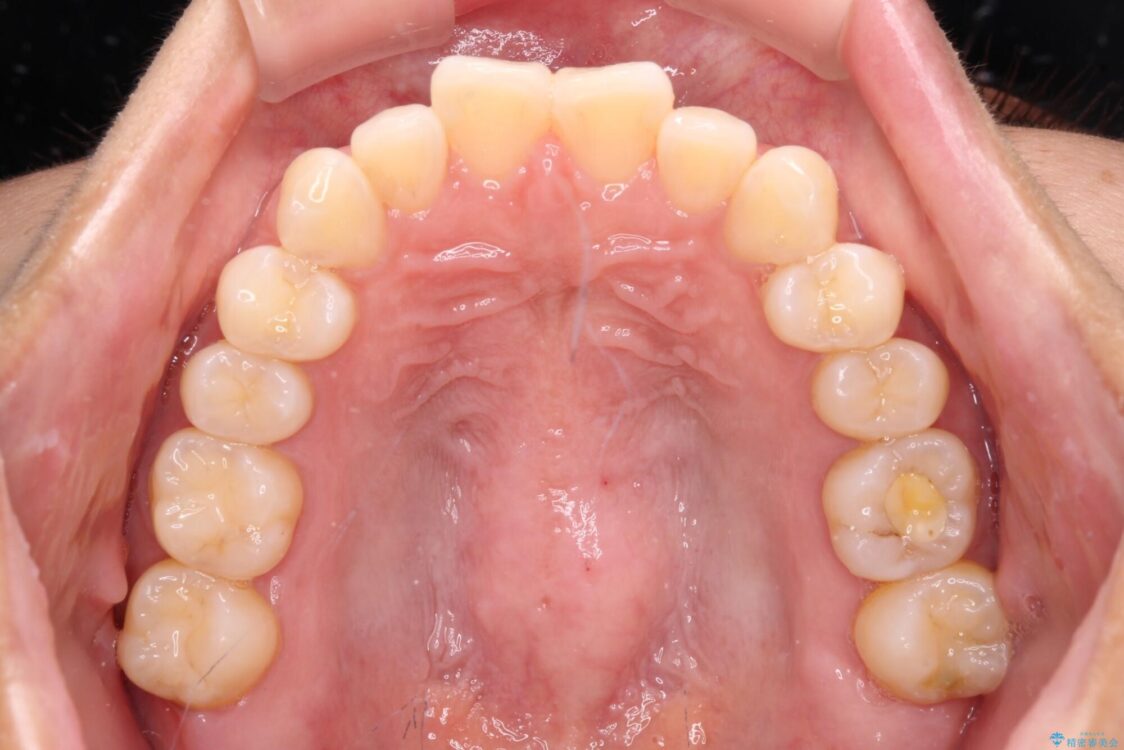

前歯のデコボコで前方に出ていることを気にして来院された患者様です。

上顎前歯が捻れて前方に飛び出しており、下顎前歯もそれに沿うようにデコボコとなっていました。

IPR(歯と歯の間を削る処置)によりスペースを獲得して上下顎前歯のデコボコを改善し、飛び出している前歯が引っ込むように設定し、インビザラインにて矯正治療を行うこととしました。

装着時間を守ってくださったので、予定通りの期間で終えることができました。インビザライン特有の、奥歯の咬み合わせの問題もなく、しっかりと歯列を改善することができました。

治療後

• 【モニター】前歯のデコボコをインビザラインで改善 治療後画像